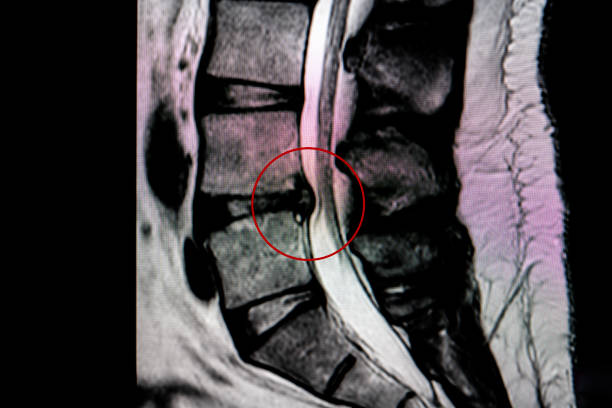

안녕하세요 저는 디스크로 인해 5번 1번 척추 내시경 수술을 받은 20대 남성입니다.

추간판 탈출증 디스크 제거 수술은 주로 디스크의 손상된 부분을 제거하는 것을 포함하며 디스크로 인해 신경의 압력을 완화하는 데 주로 사용됩니다.

척추 내시경 수술

추간판 탈출증 수술은 수술후 통증이나 재발과 같은 합병증이 나타날 수 있어 최소침습적인 수술 방법들이 발전되고 있습니다. 척추 내시경 수술은 피부에서 디스크까지 내시경을 이용해 접근하여 디스크를 제거하는 치료법으로, 보존요법과 수술요법 사이의 최적의 방법입니다. 일상생활 복귀가 빠르고 출혈이 거의 없어 수혈도 필요가 없습니다. 보통 국소 마취로 진행됨으로 전신마취의 위험이 있는 고령자나 당뇨병 환자에게서도 시행할 수 있다는 장점이 있습니다.